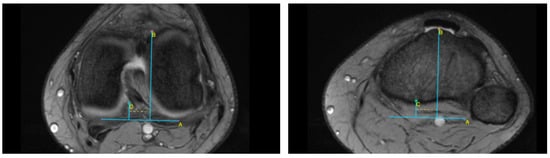

| TT–TG | tibial tuberosity–trochlear groove |

| TT–PCL | tibial tuberosity–posterior cruciate ligament |